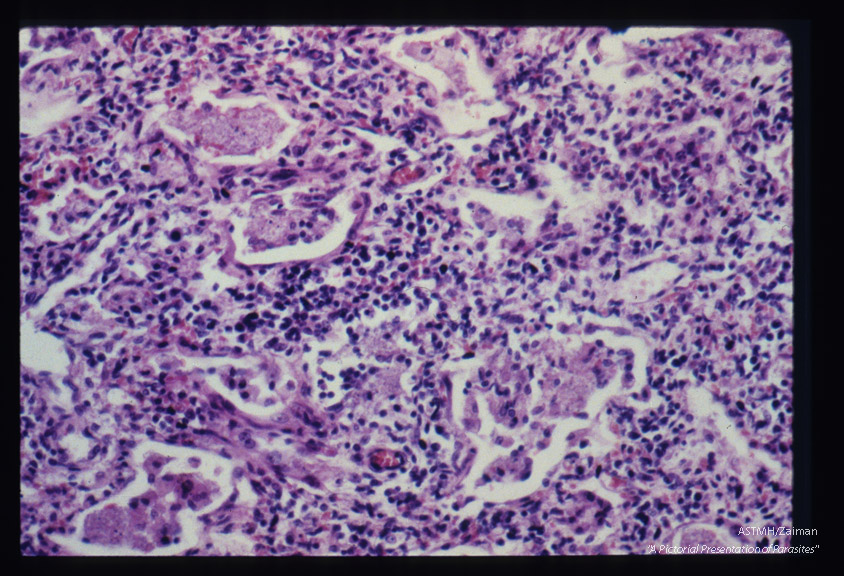

Pneumonia. Slightly larger magnification shows thickened alveolar walls invaded by large numbers of plasma cells and lymphocytes. The alveolar spaces are filled with honeycomb material. There is no neutrophilic leucocytic infiltration nor is a fibrinous deposit present.

Pneumocystis carinii